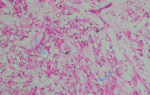

Follow-up and outcome of interventions: the patient had an uneventful recovery and was discharged home three days post-operatively. Histological review showed: a para-tubal cyst and two sections of the right fallopian tube with a lesion on the periphery, which had cells that were moderately eosinophilic with multiple vacuoles, giving signet ring cell morphology. The cells were arranged in tubules and cords. The lesion had no mitotic activity, and no features of malignancy were seen. Features were consistent with an adenomatoid tumor of the fallopian tube. No malignant cells were seen in fluid from resected pelvic and right ovarian cysts. We made a final diagnosis of pelvic inclusion cysts and an incidental adenomatoid tumor of the fallopian tube. The patient was reassured that she had a benign tumor, which was resected, and no further interventions were necessary. Contraception advice was given, and the patient was scheduled for review in three months. Upon review in the outpatient clinic, three months post-surgery, the patient was feeling much better. And pelvic pain had markedly subsided. She reported intermittent mild pain with a score of 2 (Figure 4, Figure 5)

Macroscopically, the tumors may resemble a leiomyoma and are firm, light grey masses with no capsule. Histologically, tumors cells are arranged in cords and tubules (trabecular arrangement) that are lined by cuboidal cells. The epithelial cells have large vacuoles that give them a signet ring appearance, mimicking signet ring cell carcinoma [6]. The tumors may also grow as gland-like cystic spaces lined by flattened cells in a background of connective tissue. Other presentations include angiomatoid, adenoid, and solid patterns [7]. In a study of 44 cases of ATs from female and male genital tracts, Sangoi and co-workers demonstrated that distinctive threadlike strands crossing the tubular spaces are always present [2]. Bland cytoplasm and lack of mitotic activity distinguish these tumors from malignant neoplasms. Differential diagnoses include signet ring cell tumor, lipoleiomyoma, mesothelioma, lymphangioma, and salpingitis isthimica nodosa [8]. Immunohistochemistry profile helps in improving diagnosis. ATs are typically positive for cytokeratin markers and negative for vascular markers [2]. Due to financial constraints, immunohistochemistry was not available to our patient. The prognosis of adenomatoid tumors is excellent, and no recurrences have been noted in the literature [9]. Therefore, no surgical radicality was necessary in our case. LLaparotomy approach was chosen over laparoscopic approach due to unavailability of functional laparoscopic equipment.

Figure 5: adenomatoid tumor. histology of right fallopian tube, high power image showing signet ring morphology (black arrows) and cystic spaces (blue arrows)